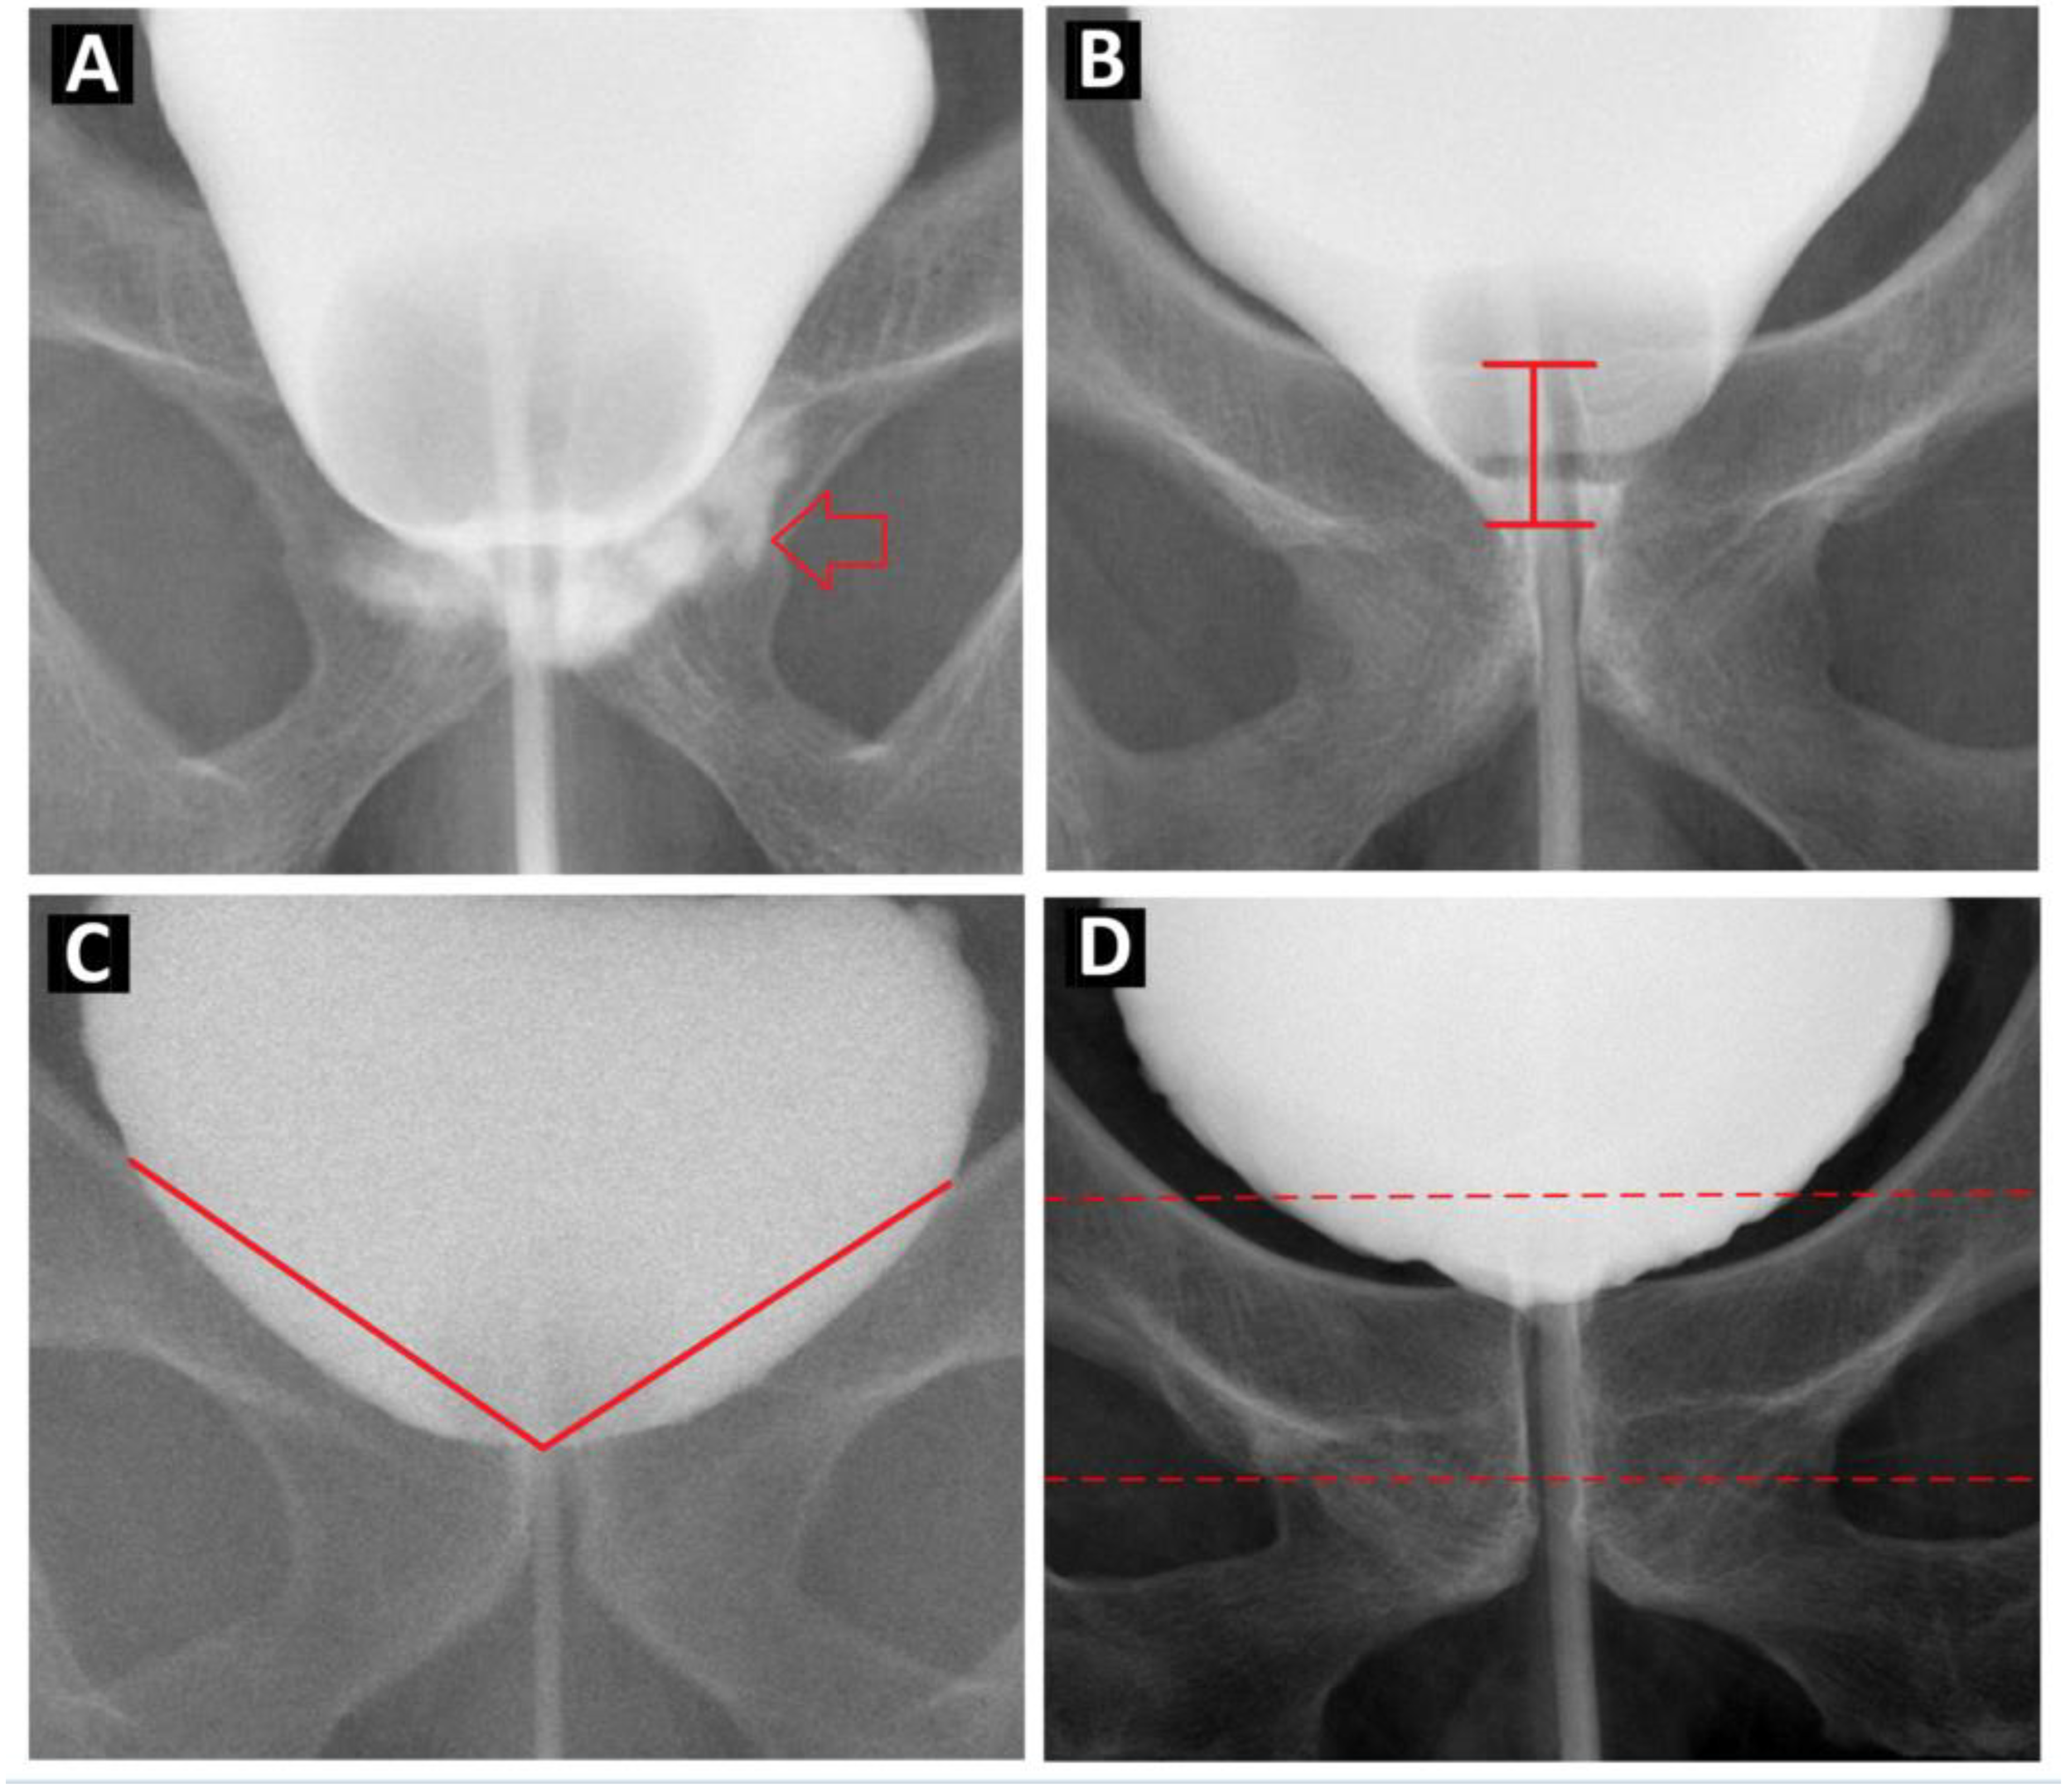

Urine leakage on cystography was indicated by contrast medium extravasation at the urethra-bladder neck junction (Figure 1A). The length of the downward bladder neck was defined as the length of the bladder neck below the lower margin of the pelvic inlet (Figure 1B). The bladder shape was described by the bladder height, bladder width, and height/width ratio. The bladder neck angle was measured as the angle between the bladder neck and the bilateral bladder margins over the pelvic inlet (Figure 1C).

2.4. Image Preprocessing

Figure 1. Illustration of Cystography feature. (A). Urinary leakage in cystography was defined as contrast leakage at bladder neck and urethra anastomosis site (red arrow). (B). The distance of downward bladder neck was defined as the length of bladder neck below the pelvic inlet lower margin, shown as the length of the red arrow between the two black horizontal lines. (C). The bladder neck angle was measured as the angle of bladder neck to bilateral bladder margin over pelvic inlet. The angle was shown as the angle between the two red lines. (D). The bilateral margin of the ROI images is the bilateral wall of the bladder, as shown in the cystography; the upper margin is the ischial spine and the lower margin is the inferior pubic ramus. Within this defined area, we adjusted the upper and lower margins of the cystography images to fit the horizontal part of the pubic bone in the middle third of the ROI images.